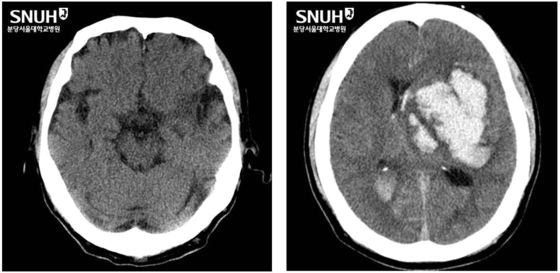

또 ‘고혈압성 뇌출혈’도 주요 원인이다. 고혈압성 뇌출혈은 뇌동맥류나 동정맥기형(출혈성 질환)과 같은 뇌혈관질환이 없더라도 고혈압으로 인해 뇌 안의 모세혈관들이 터지면서 발생하는 질환이다.

이는 한순간에 반신 마비가 되거나 의식불명, 사망까지 이르게 할 정도의 무서운 질환이라서 주로 발생하는 부위가 있기는 하나, 뇌 전반적으로 발생할 수 있다.

고혈압 뇌출혈은 출혈량이 많으면 머리를 여는 개두술을 통한 혈종제거술을 시행할 수 있다. 뇌동맥류가 원인인 경우는 재출혈을 막기 위해 ‘코일색전술’ 또는 개두술을 통한 뇌동맥류 ‘클립결찰술’을 할 수 있다.

고혈압성 뇌출혈이든 뇌동맥류 파열로 인한 뇌출혈이든 뇌부종이 심하고 뇌압이 높으면 두개골제거술을 우선 시행하고 추후에 부종이 가라앉으면 두개골을 다시 넣는 수술을 하기도 한다.